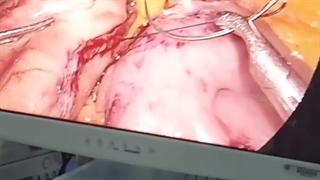

پخش صدا راهکار کاهش آمبولی بعد از عمل چاقی اشتراکگذاری لیست پخش ۰ نظر ۰ نظر دانلود دانلود ویدیو دانلود کیفیت 720p ۱۲.۰۴ مگابایت دانلود کیفیت 480p ۷.۷۵ مگابایت دانلود کیفیت 360p ۵.۵۸ مگابایت دانلود کیفیت 240p ۳.۶۹ مگابایت دانلود کیفیت 144p ۲.۵۱ مگابایت گزارش تخلف بیشتر گزینههای بیشتر لیست پخش لایکها گزارش تخلف ۰ لایک دکتر سید علیرضا آذرپیکان منتشر شده در تاریخ ۱۴۰۱/۰۵/۰۲ این کانال دنبال شد دنبال کردهاید دنبال کردن این کانال دنبال کردن برای اطلاعات بیشتر نام دکتر علیرضا آذرپیکان را در گوگل سرچ کنید و وارد سایت drazarpeikan شوید. ادامه نظرات لبخند لبخند لغو ثبت نظری برای نمایش وجود ندارد.